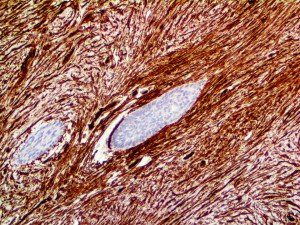

This activation induces inflammatory monocytes to highly express IL-6, starting a localized and then systemic cascade effect that results in hyperproduction of IL-6, which accelerates the inflammatory process. Because IL-6 also increases vascular permeability, excessive levels cause blood vessels to become very leaky. This, along with clotting factors released from vascular endothelial cells, stimulates the coagulation cascade, resulting in microthrombosis (tiny clots), which leads to ischemia and tissue death of the kidney, intestines, heart, liver, brain and extremities.